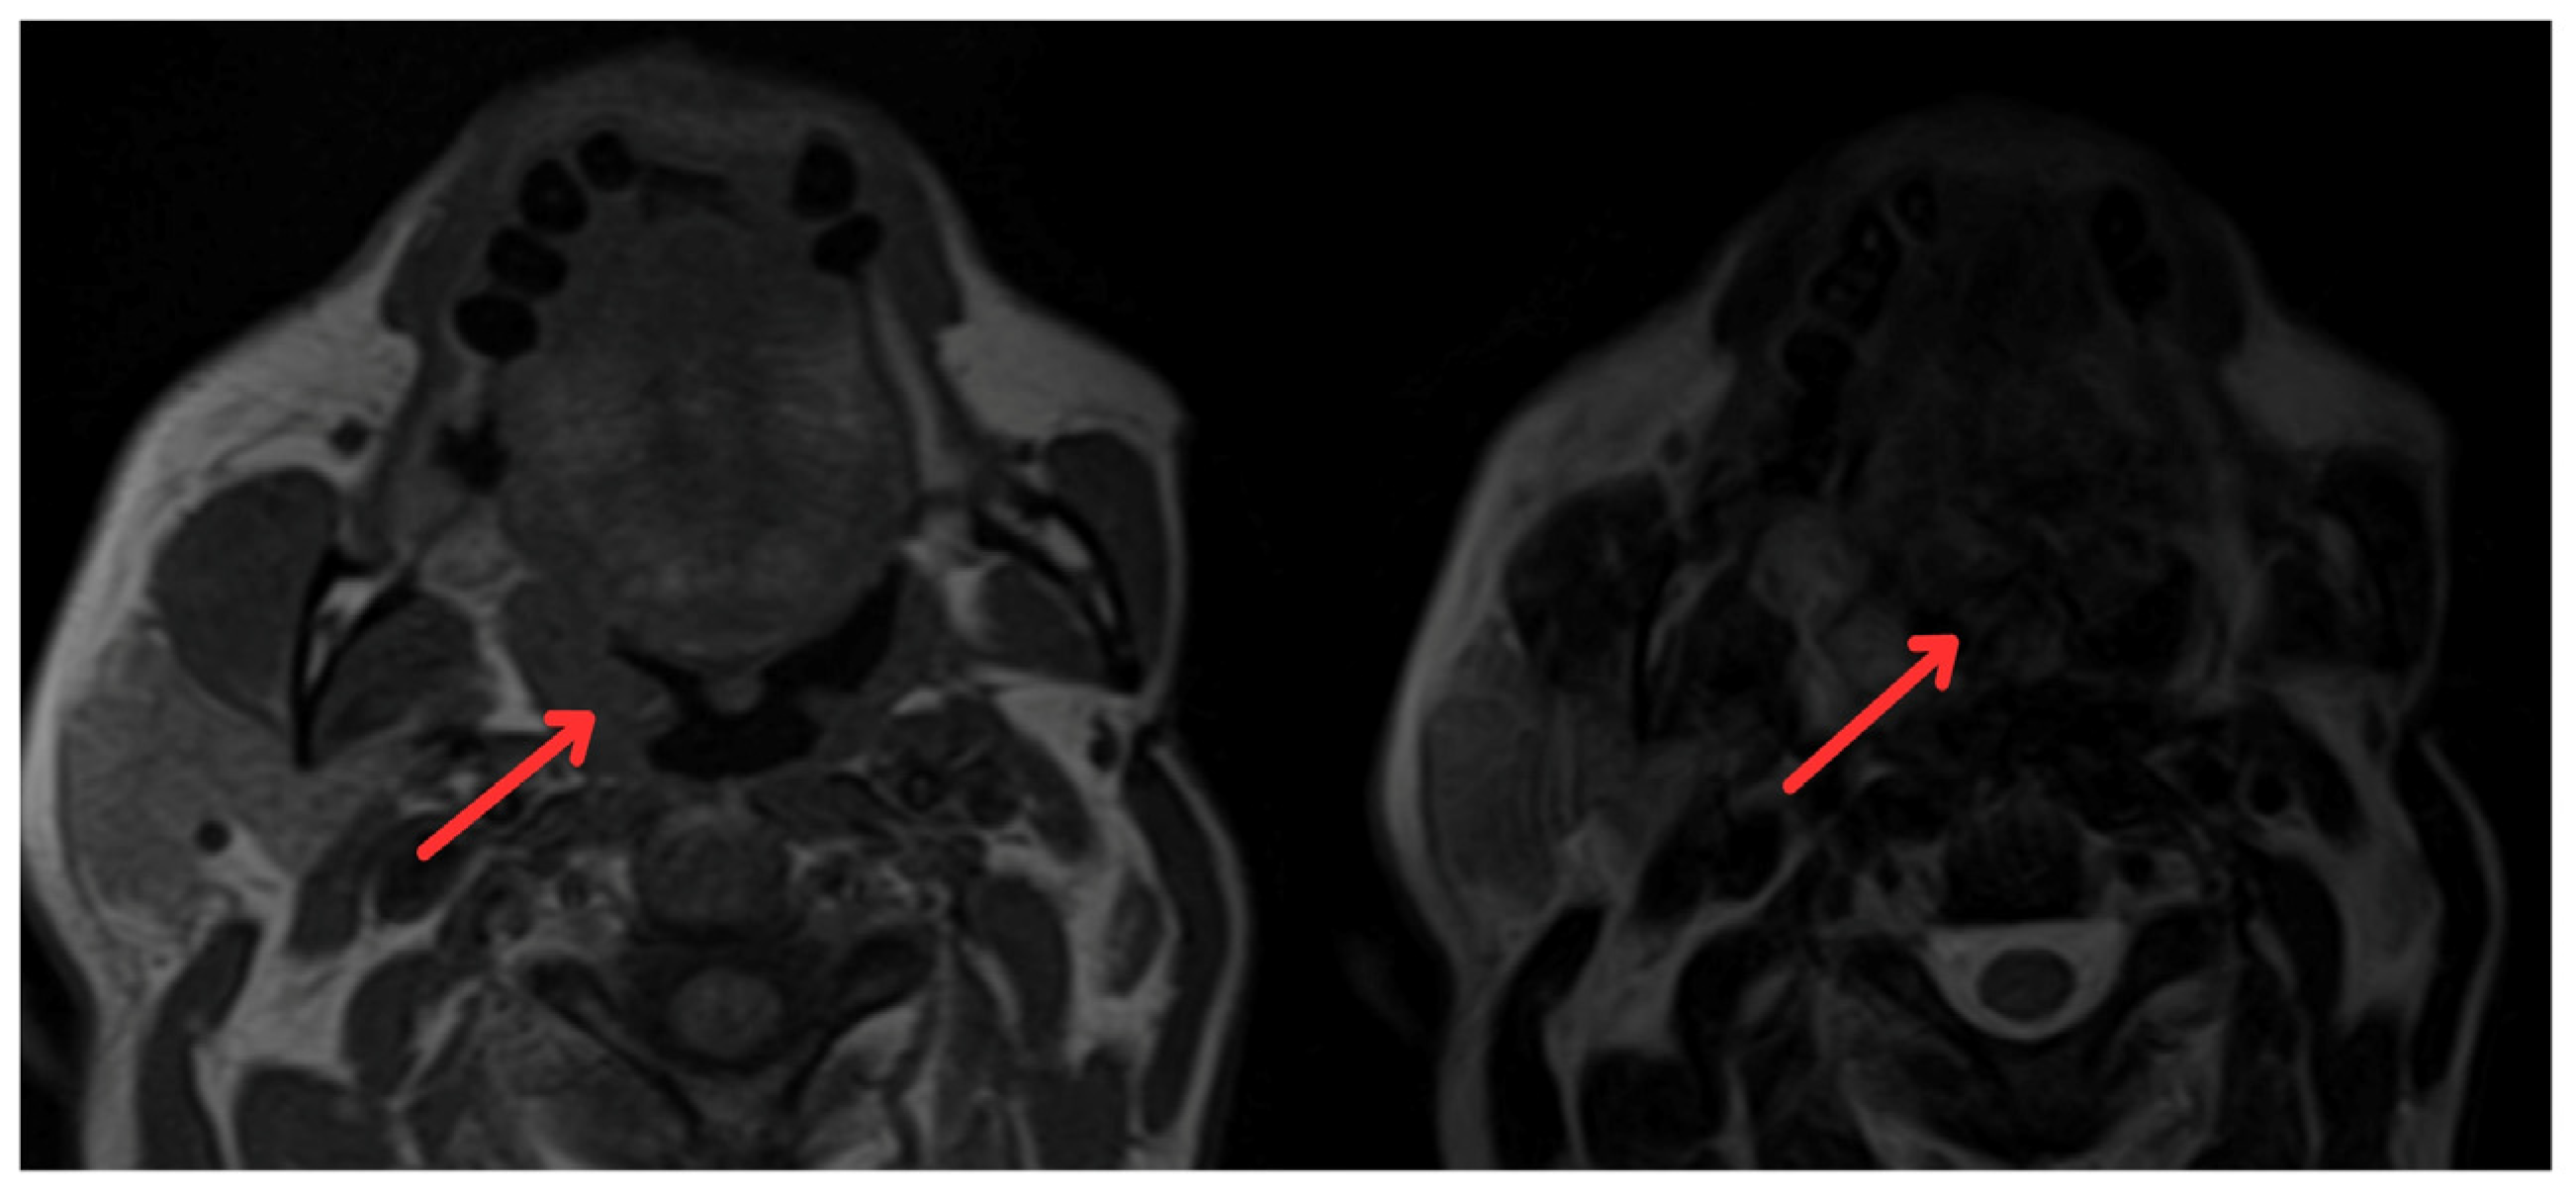

In June 2022, the head and neck surgery service, suspecting a relapse of rhabdomyosarcoma, requested nasopharyngoscopy and magnetic resonance imaging (MRI) of the paranasal sinuses (Figure 2). The reports indicated the presence of a mass with irregular enhancement affecting the mucopharyngeal space and the right palatine tonsil and extending to the tongue base with neoplastic characteristics. This led to an expanded imaging study with a contrast-enhanced neck MRI (Figure 3), which showed irregular enhancement of a mass compromising the mucopharyngeal space and the right palatoglossal arch, measuring 22 × 10 mm, similarly affecting the right palatine tonsil and extending to the tongue base with a neoplastic appearance, as well as lymphadenopathy at the right cervical station three, which was suspicious.

Figure 2.

Magnetic resonance imaging of paranasal sinuses showing irregular enhancement forming a mass that involves the mucopharyngeal space and the right palatine tonsil (red arrows).